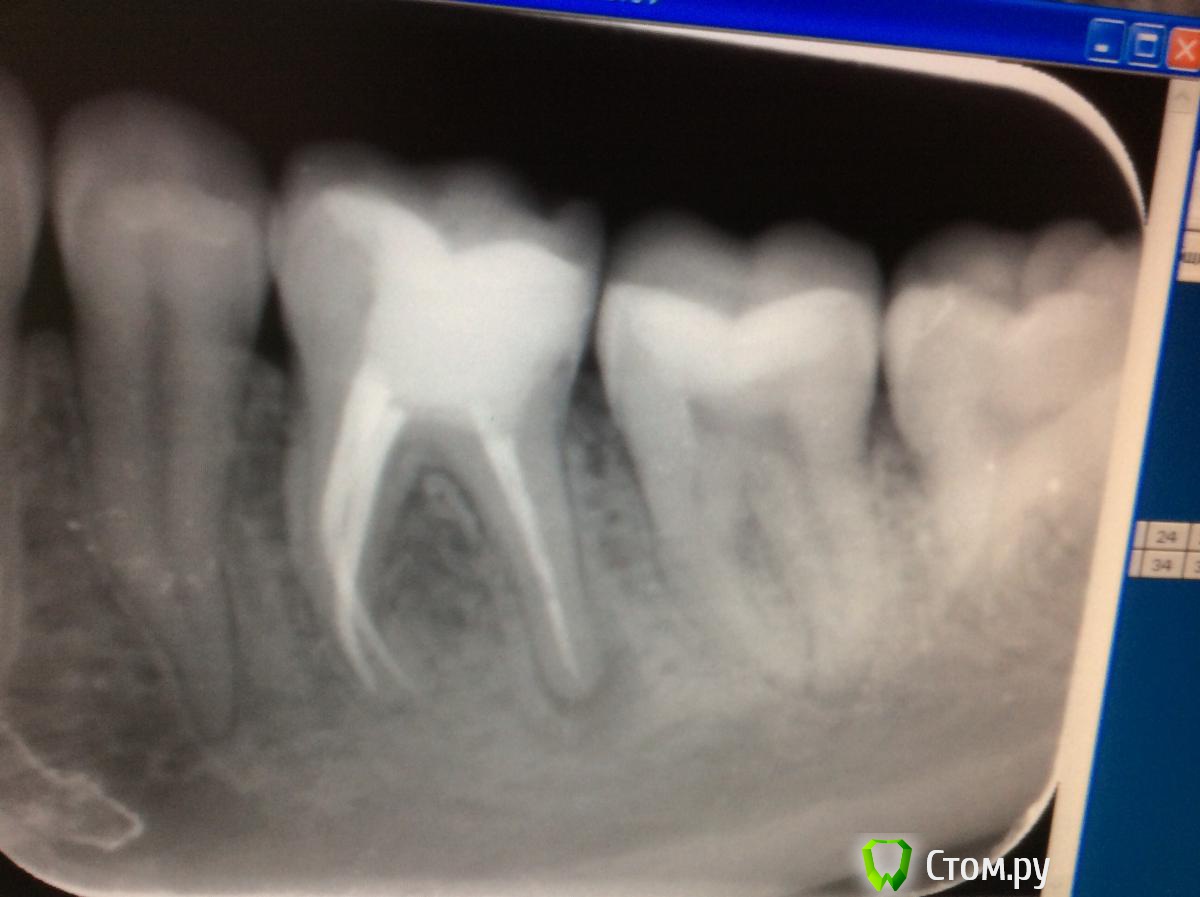

Bratok Опубликовано 18 сентября, 2014 Автор Поделиться Опубликовано 18 сентября, 2014 (изменено) Коллеги, подскажите, пожалуйста, причины возникновения болей после фиксации временной коронки. Аллергия на пластмассу? Остатки цемента могли остаться между зубами и вызвать локальный пародонтит? Зуб мог сломаться? При жевании пациент на боль не жалуется. Началось перед сном спустя несколько дней после фиксации времянки. Как будто что то давит, со слов пациента, боль постоянная. При пальпации переходной безболезненно. При перкуссии пациент отмечает дискомфорт со стороны язычных бугров. Могла быть перегрузка после фиксации? Зуб долгое время "не жевал". Снимки процесса. (Первый снимок - ситуация до лечения)Фото фиксации времянки примерно 5 дней назад.P.S. Извиняюсь за качество снимков..Размер ножки вкладки был продиктован уже имеющейся ситуацией до лечения. Изменено 18 сентября, 2014 пользователем Bratok Ссылка на комментарий